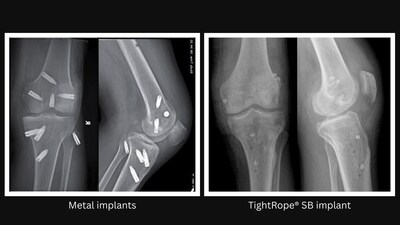

By eliminating rigid materials and preserving strong, adjustable fixation, the device expands graft-fixation options for both ACL reconstruction and repair. This less invasive approach supports improved knee stability and range of motion,1,2 while eliminating the presence of metal implants.

The all-suture, soft-button technology used in the TightRope SB implant offers high-strength fixation and features a flat-tape loop that holds the new ligament in place.2 The implant is also radiopaque, which helps surgeons confirm its position during and after surgery. The implant is available in a variety of configurations to support ACL reconstruction using all graft types as well as ACL primary repair procedures.